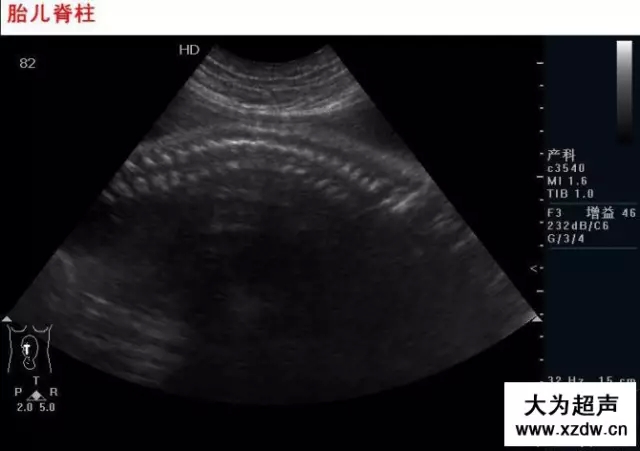

新領(lǐng)程大為超聲 早中孕期胎兒

產(chǎn)科超聲正常圖片